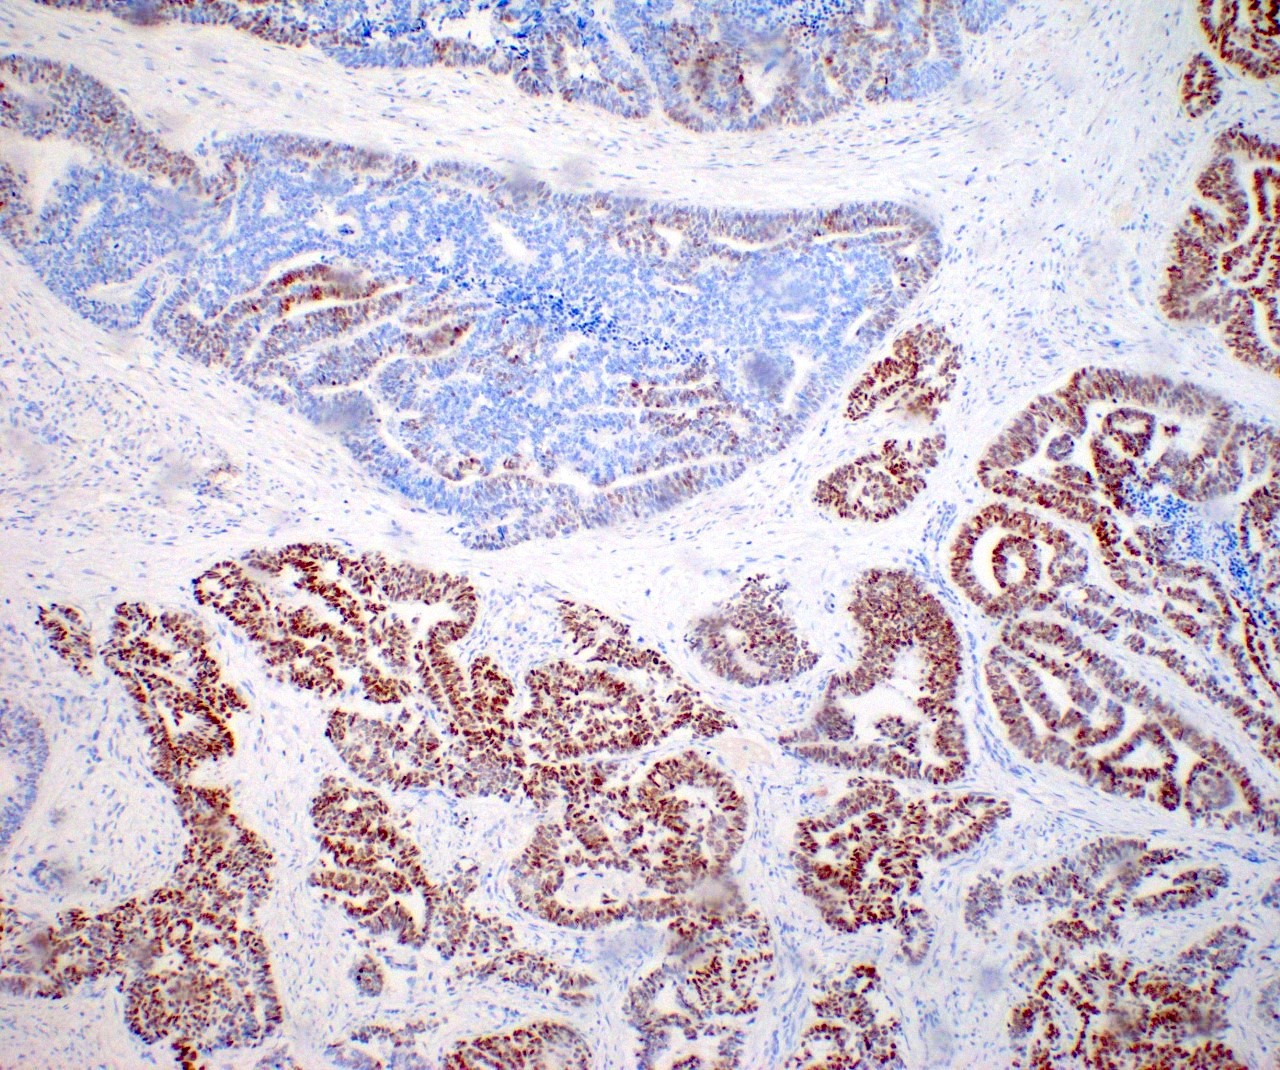

Microscopic (histologic) images

Contributed by Daniel Graham, M.D., Adele Wong, M.B., B.Ch., B.A.O. and Lucy Ma, M.D.

- GATA3 and TTF1: focal or diffuse with inverse staining pattern described in several studies in the most recent WHO classification; cells positive for GATA3 are negative for TTF1 and vice versa (Am J Surg Pathol 2018;42:1596)

Negative stains

- ER

- PR (more reliable negative marker than ER)

- Calretinin (usually negative may be focally positive)